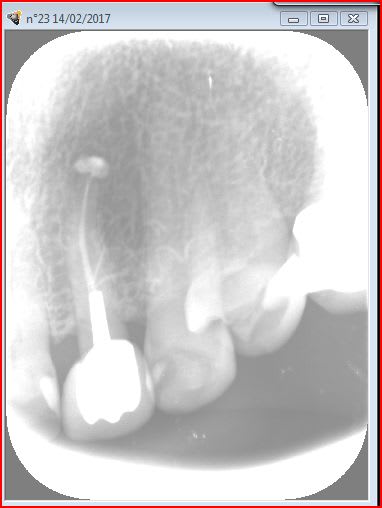

06/03/2017 à 13h51

controle de la dent de la page 8

Hoho! entre la page 8 et la page 22 tu as changé la couronne!

06/03/2017 à 14h41

oui tres rapidement apres l'époque de la page 8 .

elle est revenue pour s en faire enlever et remettre d'autres :-)).

06/03/2017 à 15h58

ha ha ha , ça fait du bien de relire ça !Elle a l'air de se porter comme un charme ta quenotte et pas une once de résorption ? mais c'est diabolique ! la mienne d'ERI je l'attends , la patiente doit passer quand ça ira mieux !